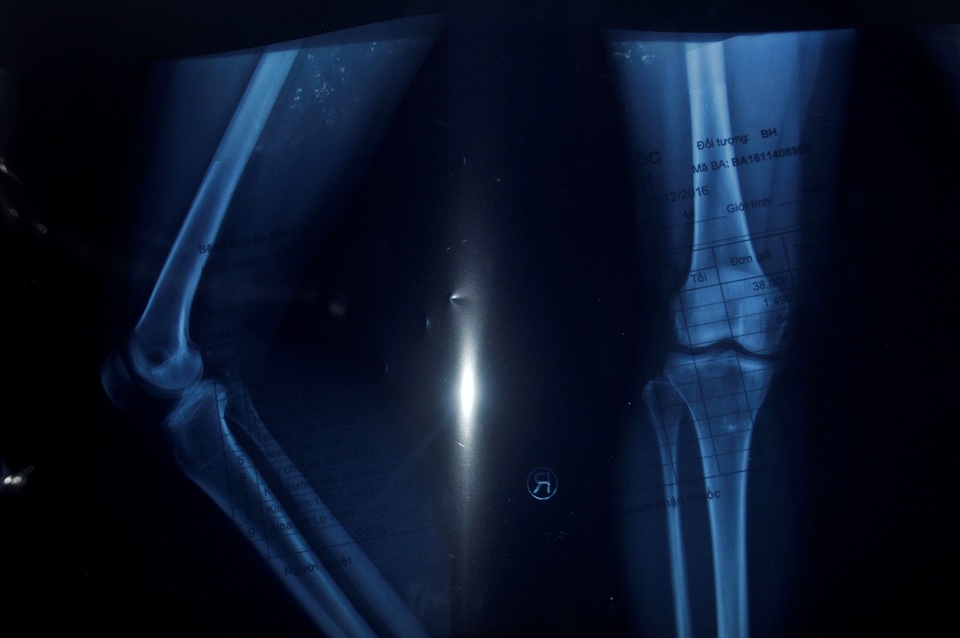

Nhưng bi kịch vẫn chưa hồi kết thúc khi cách đây gần một tháng anh được người thân chở đi trên đường thì va chạm với xe máy của một thanh niên say xỉn. Sau tai nạn, anh nằm liệt một chỗ, mọi sinh hoạt cá nhân đều phải nhờ vợ, mẹ già và những người hàng xóm tốt bụng xung quanh. Một chân bị thoái hóa xương đùi ngày càng trầm trọng, nay lại thêm gãy xương cổ tay và gãy xương ống chân cần phải phẫu thuật nếu không anh có thể vĩnh viễn mất đi hai chân của mình.

Chi phí phẫu thuật lên đến 80 triệu đồng; đây là con số quá lớn đối với gia đình thuộc diện khó khăn; trong khi đó vợ anh đang còn phải chạy ăn từng bữa cho gia đình, tiền thuốc men, tiền nợ nần sau lần anh nhập viện, lãi ngân hàng từ số tiền vợ chồng vay làm nhà sau hai lần bị bão đánh sập năm 2006 và 2013...

Không kìm được lòng, chị Nga nức nở khiến chúng tôi cũng thấy xót xa, chị tâm sự: “Anh đau và khó chịu lắm, nhiều đêm ảnh trằn trọc không ngủ được vì hai chân tê nhức nhưng cũng cố chịu đựng vì sợ vợ con lo lắng. Bác sĩ bảo chỉ có phẫu thuật mới hy vọng giữ lại đôi chân nhưng 80 triệu là con số quá lớn với gia đình. Thương anh lắm nhưng tôi cũng đành bất lực, nợ cũ cũng chưa trả xong, biết xoay sở ở đâu bây giờ”.